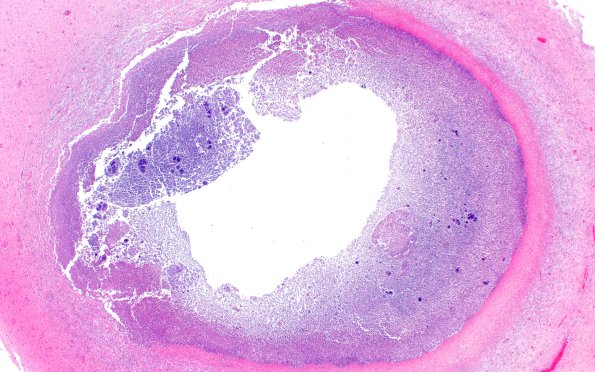

17C11 Abscess (Case 17) N13 H&E 2XA

17C11,12 Particularly photogenic small abscesses with a similar histologic appearance. (H&E)